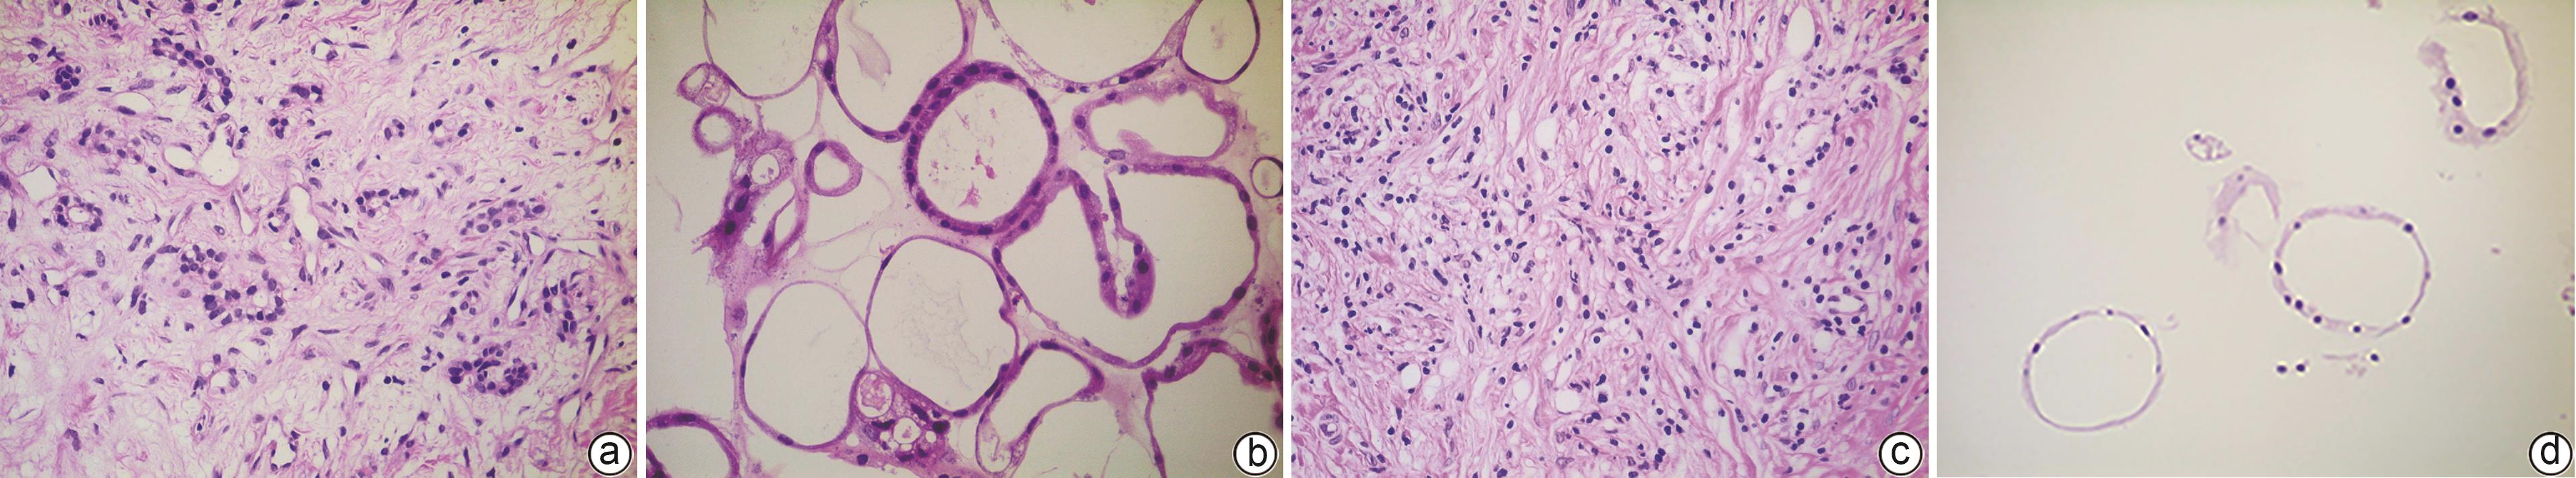

Construction of pancreatic cancer organoids and their sensitivity to chemotherapy drugs

2024, 40(9): 1853-1858. DOI: 10.12449/JCH240921

Abstract(1501) HTML (277) PDF (3800KB)(102)

Abstract:

Objective  To construct and identify a patient-derived organoid model, and to investigate the sensitivity of chemotherapy drugs using this model.  Methods  Pancreatic cancer cells were obtained from the surgical specimens of two female patients with a confirmed diagnosis of pancreatic cancer after tumor tissue digestion, and then the cells were inoculated into a culture dish using matrigel for three-dimensional culture. Paraffin sections were prepared for HE staining and immunohistochemical staining and were compared with the parent tumor tissue to determine whether the histopathological features of the tumor in vivo were preserved. The pancreatic cancer organoids were treated with seven chemotherapy drugs at different concentrations; Cell Titer-Glo®3D reagent was used to measure cell viability, and the results of drug sensitivity were analyzed.  Results  Two patient-derived pancreatic cancer organoids were successfully constructed, and HE staining and immunohistochemical staining showed that the pancreatic cancer organoids had consistent histopathological features with the tumors of the corresponding patient. Both pancreatic cancer organoids were more sensitive to gemcitabine monotherapy and the combination of oxaliplatin+SN38+fluorouracil, and patient 1 was more sensitive than patient 2. There were individual differences in the response to drugs between the organoids from different patients.  Conclusion  The pancreatic cancer organoid model successfully constructed in this study can reflect the histological classification of parent pancreatic tumors and can be used for in vitro chemotherapy drug sensitivity test, which is expected to provide a reference for clinical medication.